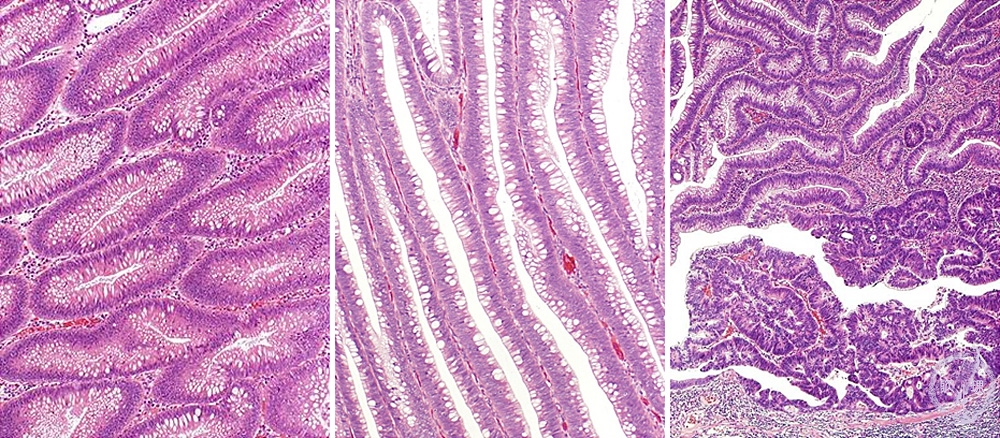

Microscopic view (H&E stain, low power): Tubular adenoma (left), villous adenoma (middle), carcinoma arising in a tubular adenoma (right)